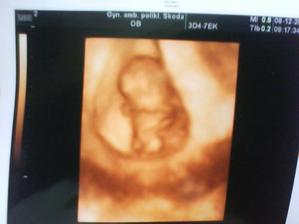

08.12.2009 10t + 2 už máme ručičky a nožičky a měříme 3cm a vše je v pořádku